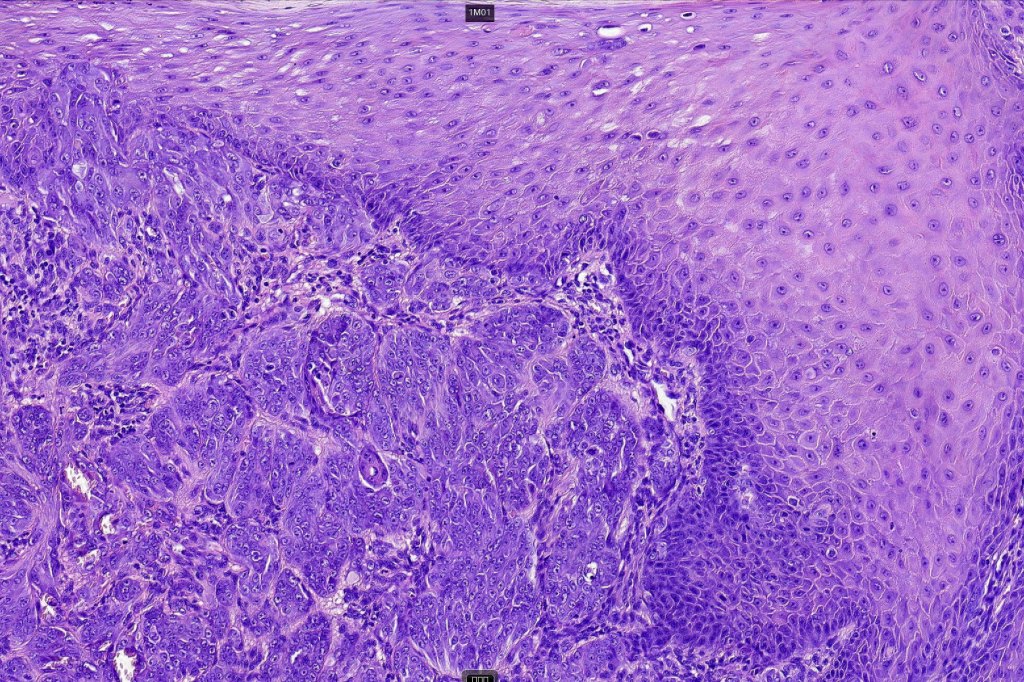

Histological features

•>5-10 mm

•Involve deep dermis or subcutis

•Asymmetrical, poorly circumscribed

•May show effacement/consumption of epidermis or ulceration

•Peripheral Pagetoid spread

•Large nodules which often show impaired maturation